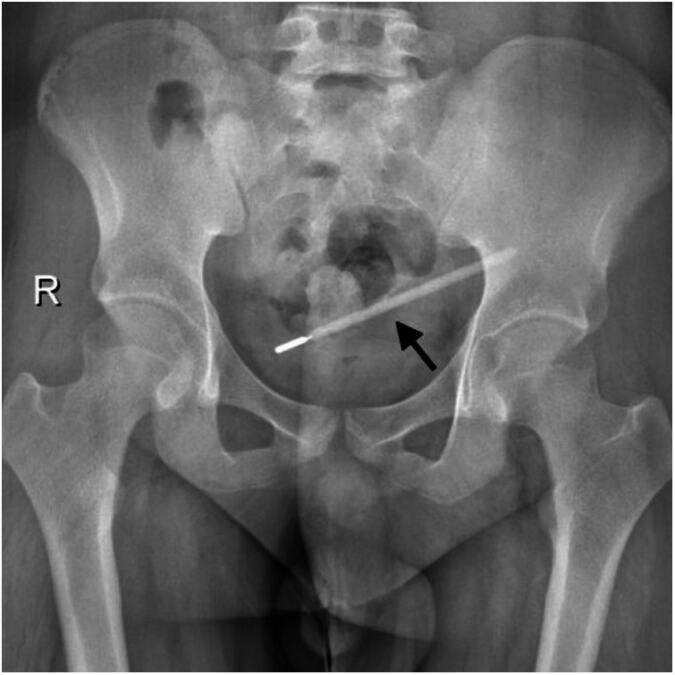

Došao u bolnicu zbog bolova u stomaku: Lekari zanemeli od šoka kad su videli šta je krio u sebi 20 godina, morao na hitnu operaciju